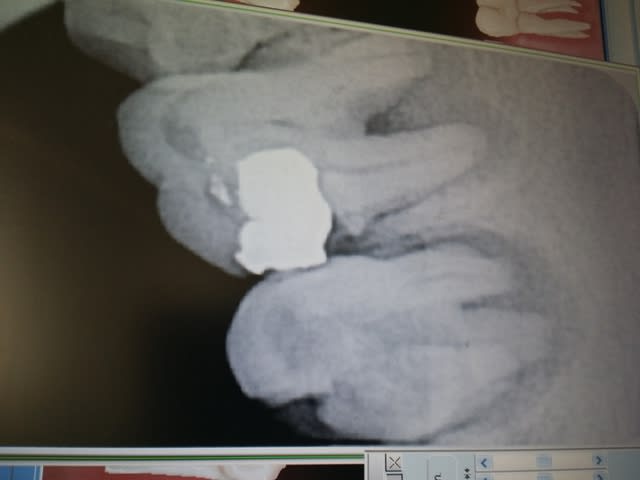

Ci joint endo sur grosse lesion, j'ai annonce' un pronostic a la patiente de 50/50...